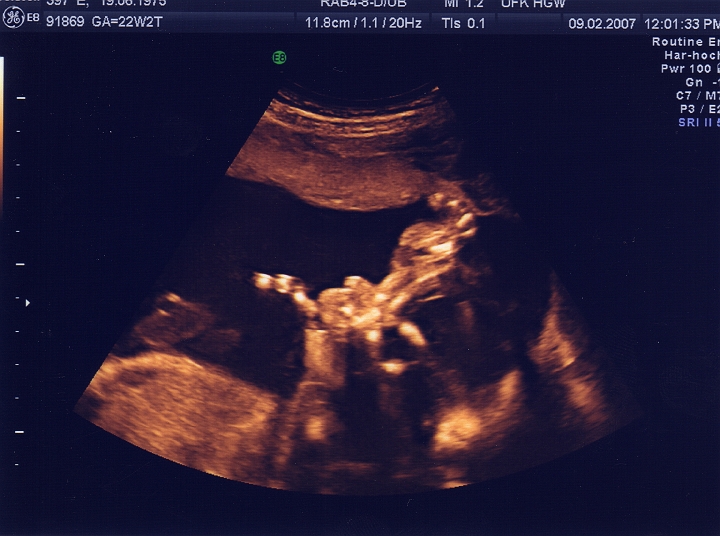

23. SSW - und ich kann schon nuckeln !